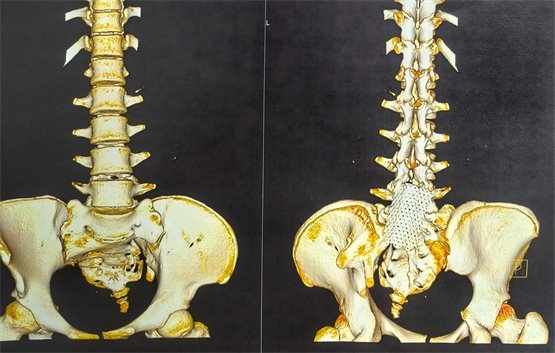

圖3為此次骶神經(jīng)電刺激穿刺前骶椎CT三維成像,可見(jiàn)骶椎裂,且骶椎扭轉(zhuǎn)畸形,根據(jù)片子可見(jiàn),手術(shù)穿刺風(fēng)險(xiǎn)及難度明顯增大